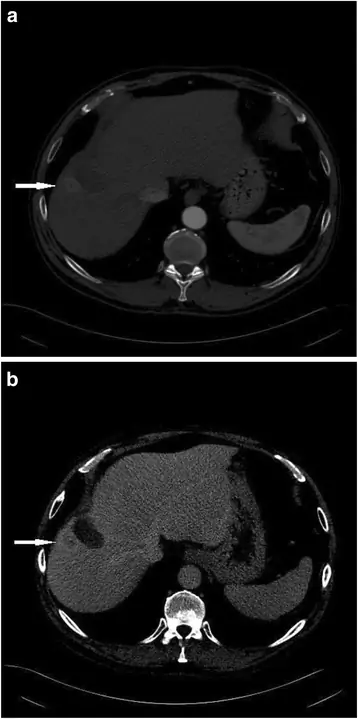

Отличительной чертой ГЦК как при КТ, так и при МРТ является позднее усиление артерии с вымыванием относительно паренхимы печени во время венозной или отсроченной фазы (через 3-5 мин после инъекции) (рис. 1). Было показано, что этот паттерн усиления демонстрирует высокую специфичность и положительную прогностическую ценность (38-40), что делает его неинвазивным стандартом диагностики ГЦК (5, 6, 35, 41-44).

фигура 1

54-летний мужчина с циррозом гепатита С. КТ показывает артериальный узелок с усилением вымывания контраста в отсроченной фазе В в соответствии с гепатоцеллюлярной карциномой

Изображение в полном размере